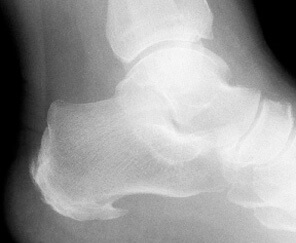

El espolón es una exostosis es decir una proliferación ósea que aparece en la parte anterior del calcáneo, en el talón.

La fascia en la región plantar se fija en la cabeza de los metatarsianos, en el calcáneo para ascender hacia la parte posterior de la pierna, ya que la fascia es un tejido que se continúa en todo el cuerpo. Una alteración de la marcha ocasionada por otra patología, una mala pisada o el uso de calzado inadecuado (abusar de zapatos de tacón) puede provocar un aumento de tensión en la fascia. Esto hace que tire más de la zona de inserción en el talón provocando la formación de tejido óseo en esta zona.